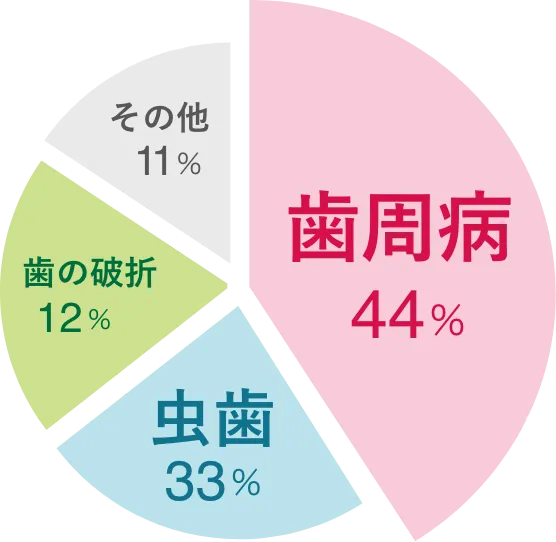

日本人が歯を失う理由の

半数近くが歯周病です

30歳以上の80%、20代でも70%近くが歯周病と言われており、

また図のように、日本人が歯を失う理由の約40%を占めています。

「私は大丈夫」と何もしないのではなく、お口のお悩みのない毎日のため、日々の予防や定期的な検査で、しっかりと歯を守りましょう。